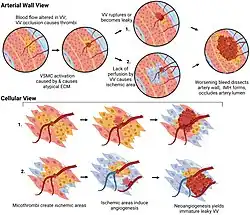

Involvement of the Vasa Vasorum

While the molecular mechanisms that underpin SCAD are still poorly understood, studies have implicated dysfunction of the vasa vasorum, the microvessels that perfuse the muscular layer of the coronary artery, lead to the bleed. There is an inverse correlation between the amount of vasa vasorum present in regions of the coronary artery and the likelihood of an area being affected by a SCAD.[1] It has been hypothesized that alterations in vessel wall strength, owing to dysfunction in the TGF-β pathway, the extracellular matrix, and vascular smooth muscle cell contractility alter the capacity of the vasa vasorum to perfuse the vessel wall, leading to either (1) a potential microthrombi and bleed, or (2) an area of hypoxia, which would likely induce new microvessel formation angiogenesis of new immature (and thus leaky) vessels.[1]

It is likely that both genetics and environment play a role in SCAD onset. A number of genetic variants have been linked to an increased the risk of SCAD. As with dissection (medical) generally, the genes identified implicate dysfunction in four main cellular molecular pathways: the TGF-β pathway,[13] extracellular matrix pathway, vascular smooth muscle cell contractility, and cellular metabolism.[1] Variants in genes including ALDH18A1, COL3A1, COL4A1, FBN1 and ACVR1 were implicated in a study of 91 unrelated SCAD cases.[13]